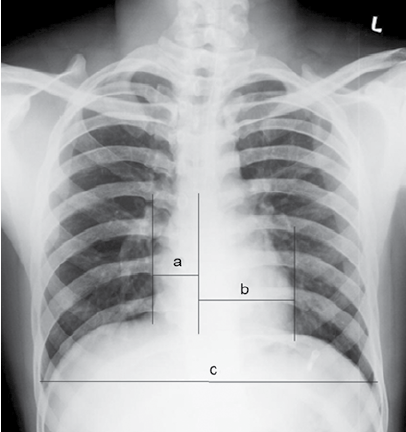

- 2단계: 수직선 그리기: X-ray 중간 (척추) 부위를 기준으로 위아래로 드래그하여 수직선을 그립니다

- 3단계: (a), (b) 선 그리기: 수직선에서 시작하여 좌우 심장 음영의 가장 튀어나온 부분까지 선을 그립니다 (순서 상관없음)

- 4단계: (c) 선 그리기: 흉곽의 가장 넓은 부분을 선택하여 수평으로 선을 그립니다

CT ratio 계산 공식:

CT ratio = ((a) + (b)) / (c) × 100

※ (a), (b): 좌우 심장 폭, (c): 흉곽 폭